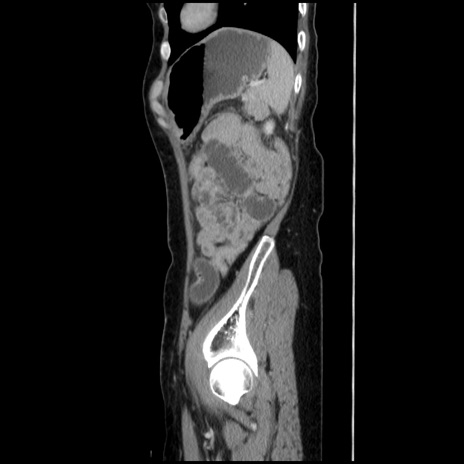

冠状断像

【症例】40歳代 女性

【主訴】上腹部痛、嘔気・嘔吐

【現病歴】約9時間前頃から急に上腹部痛、嘔気、嘔吐が出現。改善しないため救急要請。

【既往歴】子宮頚癌(広汎子宮全摘術、放射線療法)、腸閉塞

【身体所見】腹部:平坦、軟、腸雑音亢進、上腹部を中心に腹部全体に圧痛あり。

【データ】WBC 8400、CRP 0.03